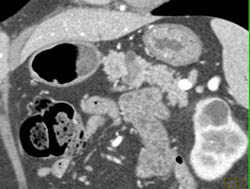

Islet Cell Tumor With Liver Metastases